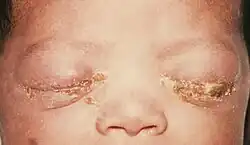

| A newborn with gonococcal ophthalmia neonatorum | |